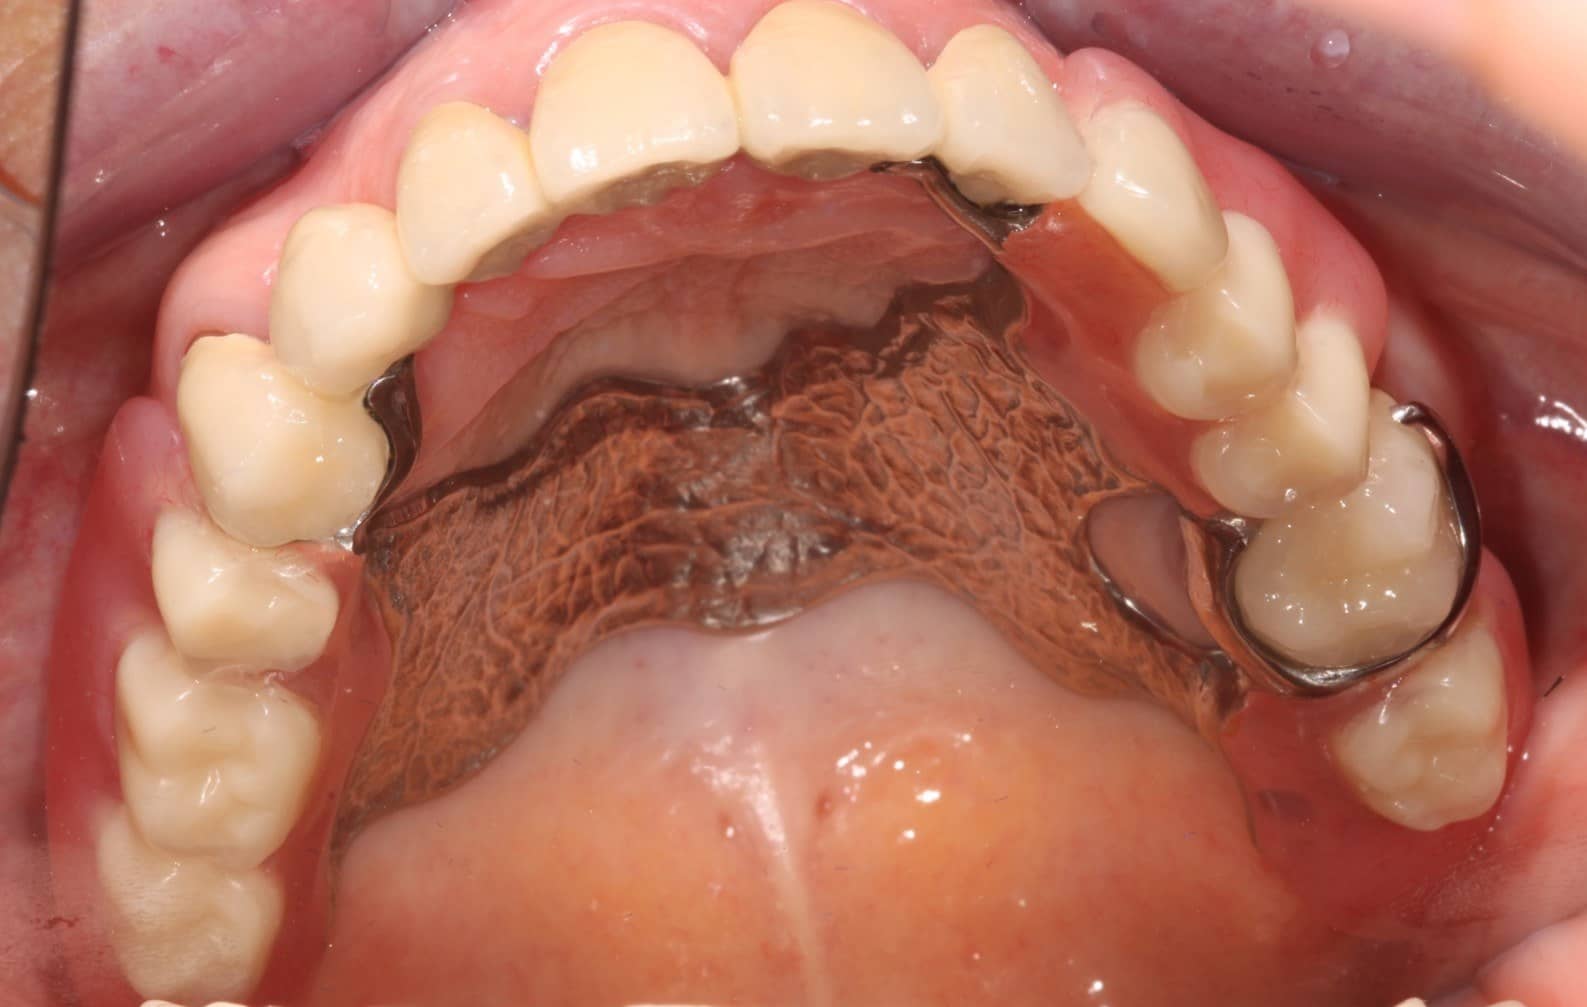

A felső állcsontra finommechanikai (Preci-Vertix) és öntött kapocs elhorgonyzású kombinált fogpótlás készült.